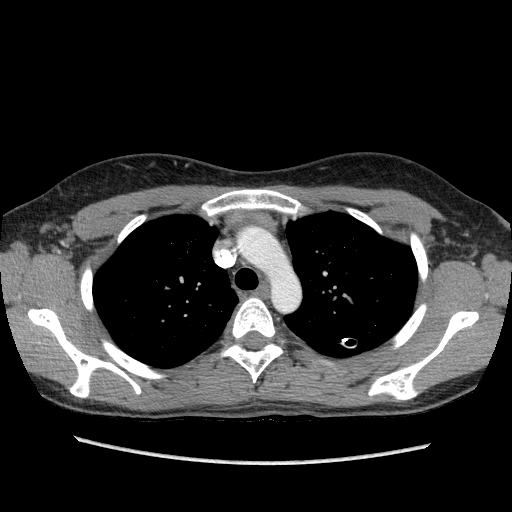

Коллеги помогите определиться. Девушка 1987 г.р. Со спонтанным пневмотораксом. Данных за миастению нет. На КТ случайная находка образование в переднем средостении. Похоже на тимому? или гиперплазия...

Тип: Клиническое наблюдение

Область: Грудная клетка и верхние дыхательные пути

Модальность: КТ